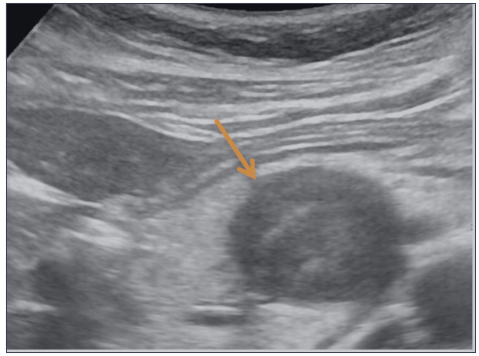

59 岁女性,已婚,无手术史,体格检查完全正常。CA19-9 肿瘤血清标志物和癌胚抗原均为阴性。腹部超声检查显示在胰腺头部有一个圆形病变,回声较低且不均匀。

图 1.1 胰头部肿瘤,呈低回声

超声检查显示在胰腺头部有一个低回声肿瘤,直径 4.0 厘米。对比前 CT 显示,该肿瘤是一个界限清楚的低密度病变,具有高密度成分(图 a)。对比注射后,病变显示不均匀的低密度,中心有高密度成分(图 B)。磁共振成像显示肿瘤在 T1 加权序列上呈均匀低信号(图 C),在 T2 加权序列上呈非均匀高信号和低信号区域(图 D)。这些影像学表现提示存在不同阶段的出血和退行性改变,包括囊肿的形成。该肿瘤,根据临床表现和影像学特征,被怀疑为一种实性-假性乳头状肿瘤(SPN)。